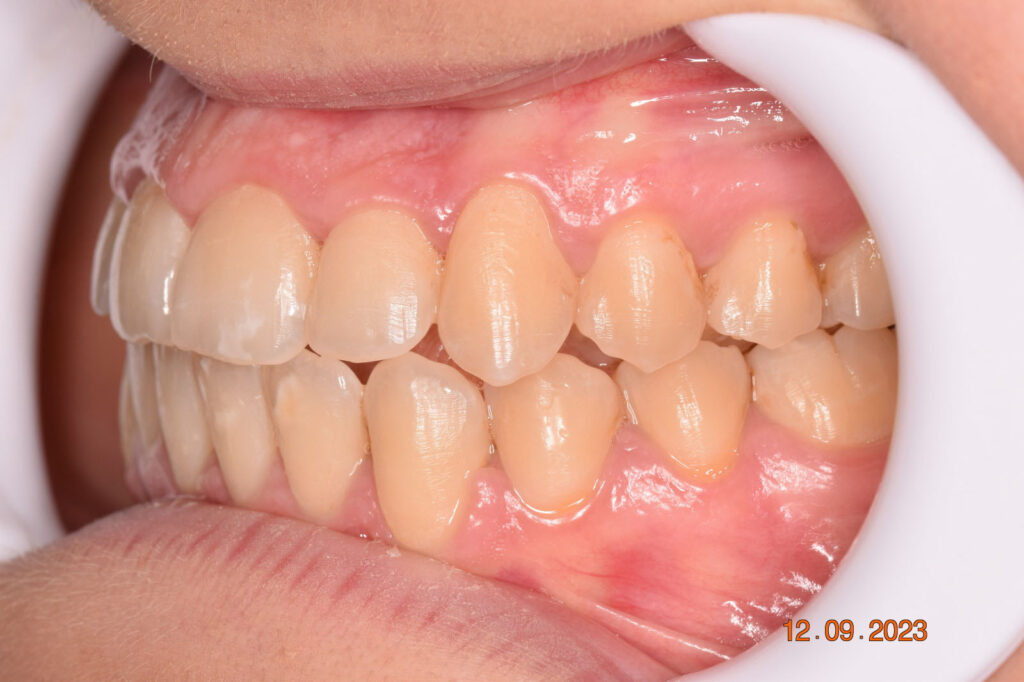

The teeth are in a very good position and the bone has reshaped.

This case posed challenges in all three spatial dimensions, compounded by significant crowding. The patient was highly compliant and maintained excellent oral hygiene throughout the 5.5 years of treatment, which required more than 30 clinical appointments.

The facial changes are impressive considering treatment involved only conventional orthodontics and not orthopedic interventions, TADs, or surgery.